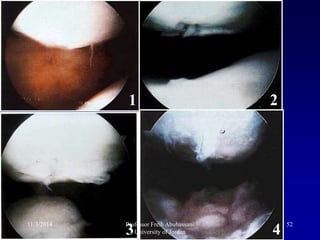

Articular degeneration

1 2

3 4

• 51.

Articular degeneration 11/3/2014 51ProfessorFreih Abuhassan- University of Jordan

• 52.

1 2 3 4 11/3/201452Professor Freih Abuhassan- University of Jordan